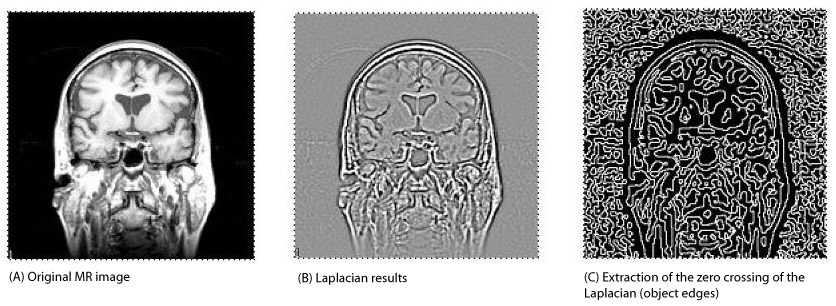

Figure 2. (A) Original MR image; (B) laplacian results; and (C) extraction of the zero crossing of the laplacian (object edges)